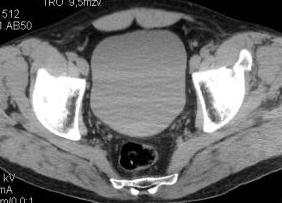

Уважаемые коллеги! Хотелось бы услышать ваше мнение. Мужчина 50л поступил с переломами костей таза. Закрытый перелом крыла подвздошной кости, переднего края вертлужной впадины справа.

Достаточно ли консервативного лечения, стоит ли беспокоиться о переднем крае? В приложении КТ.

По предоставленым снимкам верифицировать повреждение невозможно.

Покажите обзорный снимок таза и проекции Judet.

Если уж делали КТ, то наверное сохранились сами срезы.